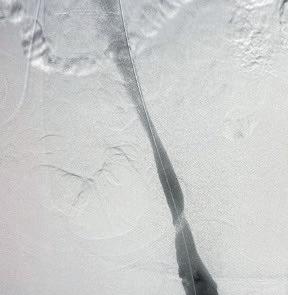

Pre-procedural venogram shows the extent of thrombus burden (1); postClotTriever venogram (2); thrombus extracted (3); pre-procedural IVUS shows extent of thrombus (4); and post-procedural IVUS demonstrates complete thrombus removal (5)

A woman in her early 60s presented with right leg pain and swelling. An ultrasound revealed unilateral right iliofemoral DVT, and the decision to intervene using the ClotTriever BOLD Catheter was made.

Procedural overview

The right popliteal vein was accessed with a micropuncture needle and wire under ultrasound guidance, and exchanged for a microsheath, ultimately upsizing to a short 10F sheath. A venogram demonstrated significant thrombus within the femoropopliteal segment, common femoral vein and extending into the external iliac vein. The lesion was crossed into the inferior vena cava (IVC). Next, pullback intravascular ultrasound (IVUS) from the IVC to the access site was performed to identify the extent of thrombus. A glidewire was advanced up into the right subclavian vein, and a vertebral catheter was advanced over it. Next, the glidewire was exchanged for a guidewire 7cm tip. A 19F dilator was used, followed by insertion of the ClotTriever sheath. The funnel was deployed under fluoroscopic guidance and the ClotTriever BOLD Catheter was advanced into the popliteal vein. The nitinol coring element and mesh collection bag were then deployed at the iliac vein, and the catheter was then retracted, capturing and removing significant acute thrombus. In total, four ClotTriever BOLD passes were completed. Completion IVUS showed complete thrombus removal. Completion venogram demonstrated brisk cephalad flow. Total procedure time was 35 minutes, while total device time was 10 minutes. There was estimated total blood loss of 20ml.

Conclusion

The patient’s pain resolved immediately postprocedure, with the swelling improving greatly. In followup, the swelling was resolved and the patient is doing well.